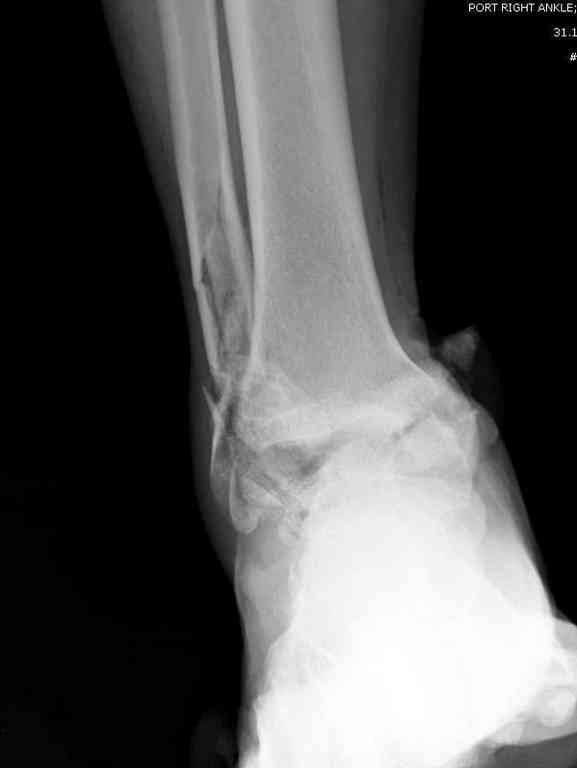

Второй случай прооперирован вчера.

10 дней назад поступил с открытым повреждением медиальной лодыжки и переломо вывихом таранной кости. Ургентно сделана репозиция с наложением наружного фиксатора + Irrigation&Debridment.

Во время репозиции выявили повреждение заднего сухожилия м. тибиалис и задней большеберцовой артерии. Медиальную рану удалось закрыть частично и установлен вакуум.

Дважды провели Irrigation&Debridment с заменой вакуума.

Вчера провели фиксацию.